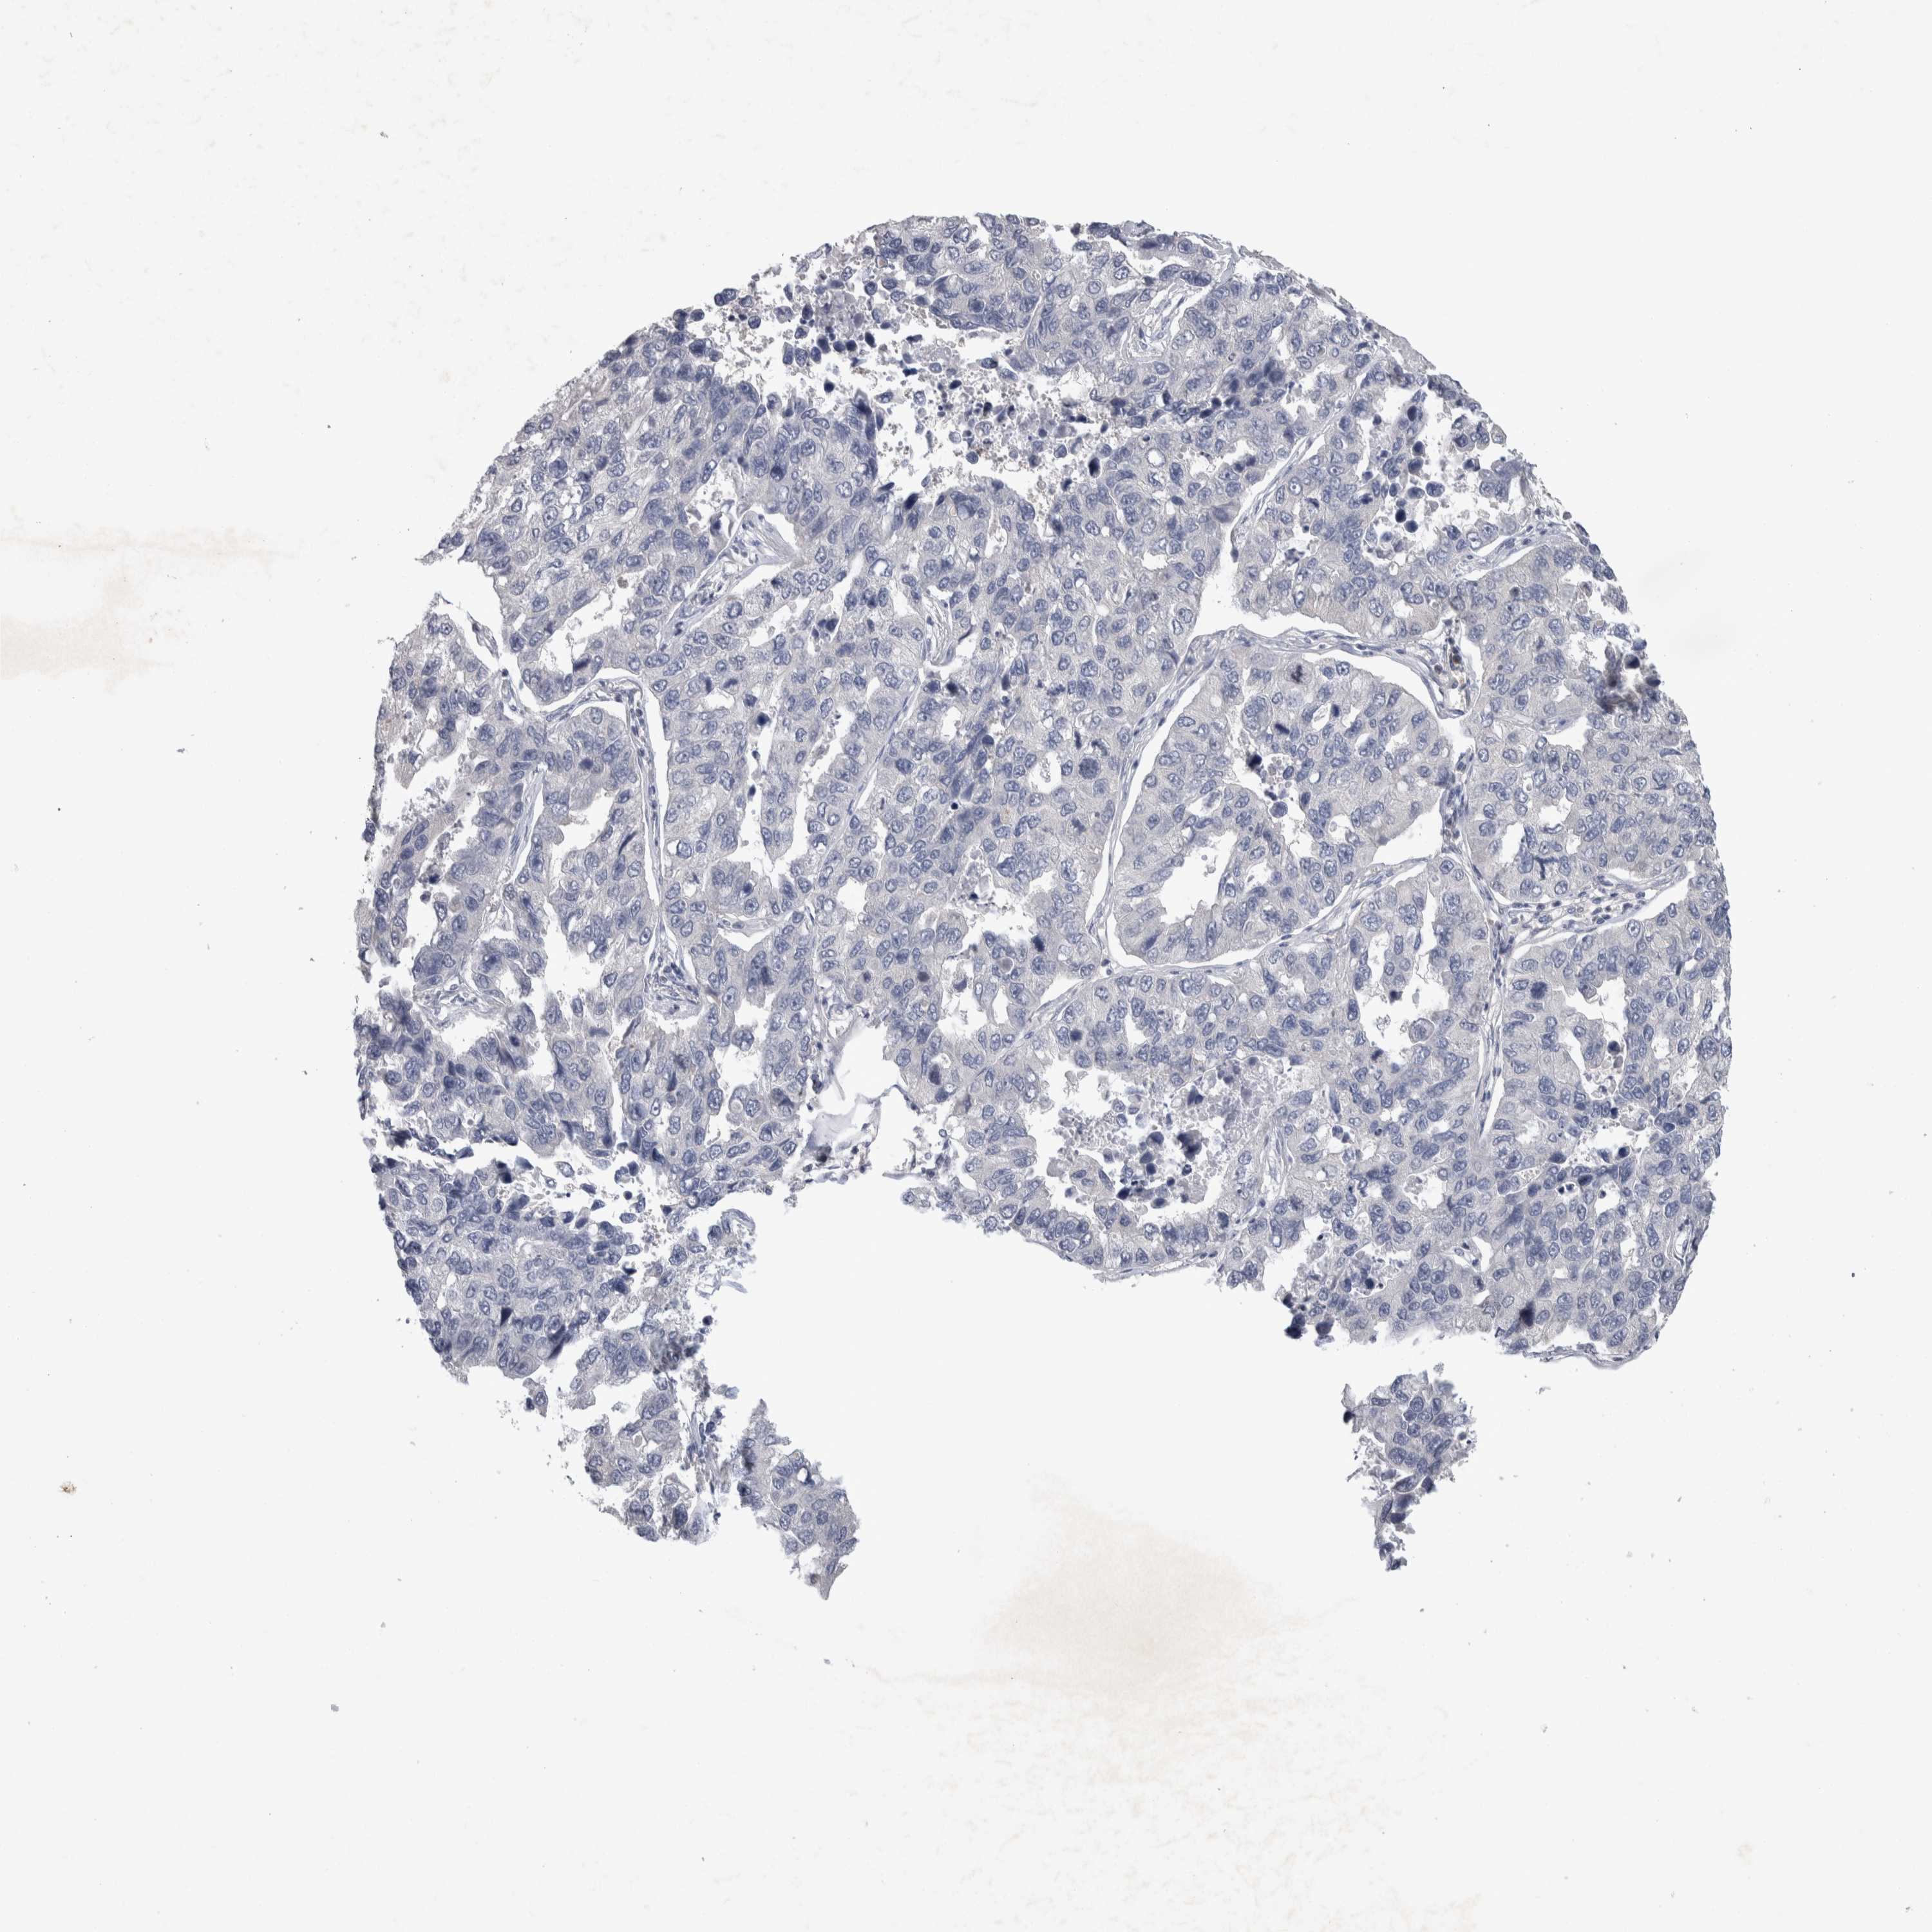

LUNG ADENOCARCINOMA (TCGA) - Interactive survival scatter ploti

The Survival Scatter plot shows the clinical status (i.e. dead or alive) for all individuals in the patient cohort, based on the same data that underlies the corresponding Kaplan-Meier plots. Patients that are alive at last time for follow-up are shown in blue and patients who have died during the study are shown in red.

The x-axis shows the expression levels (FPKM) of the investigated gene in the tumor tissue at the time of diagnosis. The y-axis shows the follow-up time after diagnosis (years). Both axes are complimented with kernel density curves demonstrating the data density over the axes. The top density plot shows the expression levels (FPKM) distribution among dead (red) and alive patients (blue). The right density plot shows the data density of the survived years of dead patients with high and low expression levels respectively, stratified using the cutoff indicated by the vertical dashed line through the Survival Scatter plot. This cutoff is automatically defined based on the FPKM cutoff that minimizes the p-score. The cutoff can be changed by dragging the vertical line or by entering a cutoff value in the square labeled "Current cut-off".

Under the Survival Scatter plot the p-score landscape (black curve; left axis) is shown together with dead median separation (red curve; right axis). Dead median separation is the difference in median mRNA expression between patients who have died with high and low expression, respectively. It is calculated as follows: median FPKM expression of dead patients with high expression - median FPKM expression of dead patients with low expression. This is intended to aid the user in visually exploring custom cutoffs and the associated p-scores and dead median separation.

Individual patient data is displayed and can be filtered by clicking on one or more of the category buttons on the top of the page. Categories describing expression level and patient information include: high, low, alive, dead, female, male and tumor stages. The scale of the x-axis can be toggled between linear and log-scale by clicking on the "x log" button. Mouse-over function shows TCGA ID, patient information and mRNA expression (FPKM) for each patient.

& Survival analysisi

Kaplan-Meier plots summarize results from analysis of correlation between mRNA expression level and patient survival. Patients were divided based on level of expression into one of the two groups "low" (under cut off) or "high" (over cut off). X-axis shows time for survival (years) and y-axis shows the probability of survival, where 1.0 corresponds to 100 percent.

NFKB2 is not prognostic in Lung Adenocarcinoma (TCGA)

Current cut offi

Current cut-off shows the cut-off (FPKM) currently selected. It may be changed manually. When the current cut-off is changed, the vertical dashed line indicating cut-off, the interactive survival scatter plot and the Kaplan-Meier curve will be automatically adjusted to show results accordingly.

:

Best expression cut offi

Based on the FPKM value of each gene, patients were classified into two groups and association between prognosis (survival) and gene expression (FPKM) was examined. The best expression cut-off refers the FPKM value that yields maximal difference with regard to survival between the two groups at the lowest log-rank P-value. Best expression cut-off was selected based on survival analysis .

When clicking on this number, the vertical dashed line indicating cut-off, the interactive survival plot, and the Kaplan-Meier curve will be adjusted to show results based on the best expression cut-off.

: 34.9

Median expressioni

Median expression refers to the median FPKM value calculated based on the gene expression (FPKM) data from all patients in this dataset. When clicking on this number, the vertical dashed line indicating cut-off, the interactive survival plot, and the Kaplan-Meier curve will be adjusted to show results based on the median expression.

: N/A

Median follow up timei

Median follow up time refers to the median time (years) after diagnosis with this type of cancer, based on clinical data from all patients in this dataset.

P scorei

Log-rank P value for Kaplan-Meier plot showing results from analysis of correlation between mRNA expression level and patient survival.

N/A

5-year survival highi

5-year survival for patients with higher expression than the expression cutoff.

For melanoma and glioma, 3-year survival is shown.

5-year survival lowi

5-year survival for patients with lower expression than the expression cutoff.

TCGA RNA samplesi

RNA-seq data is reported as average FPKM (number Fragments Per Kilobase of exon per Million reads), generated by the The Cancer Genome Atlas (TCGA) .

Normal distribution across the dataset is visualized with box plots, shown as median and 25th and 75th percentiles. Points are displayed as outliers if they are above or below 1.5 times the interquartile range. FPKM values of the individual samples are presented next to the box plot.

Average pTPM 29.7

Number of samples 497